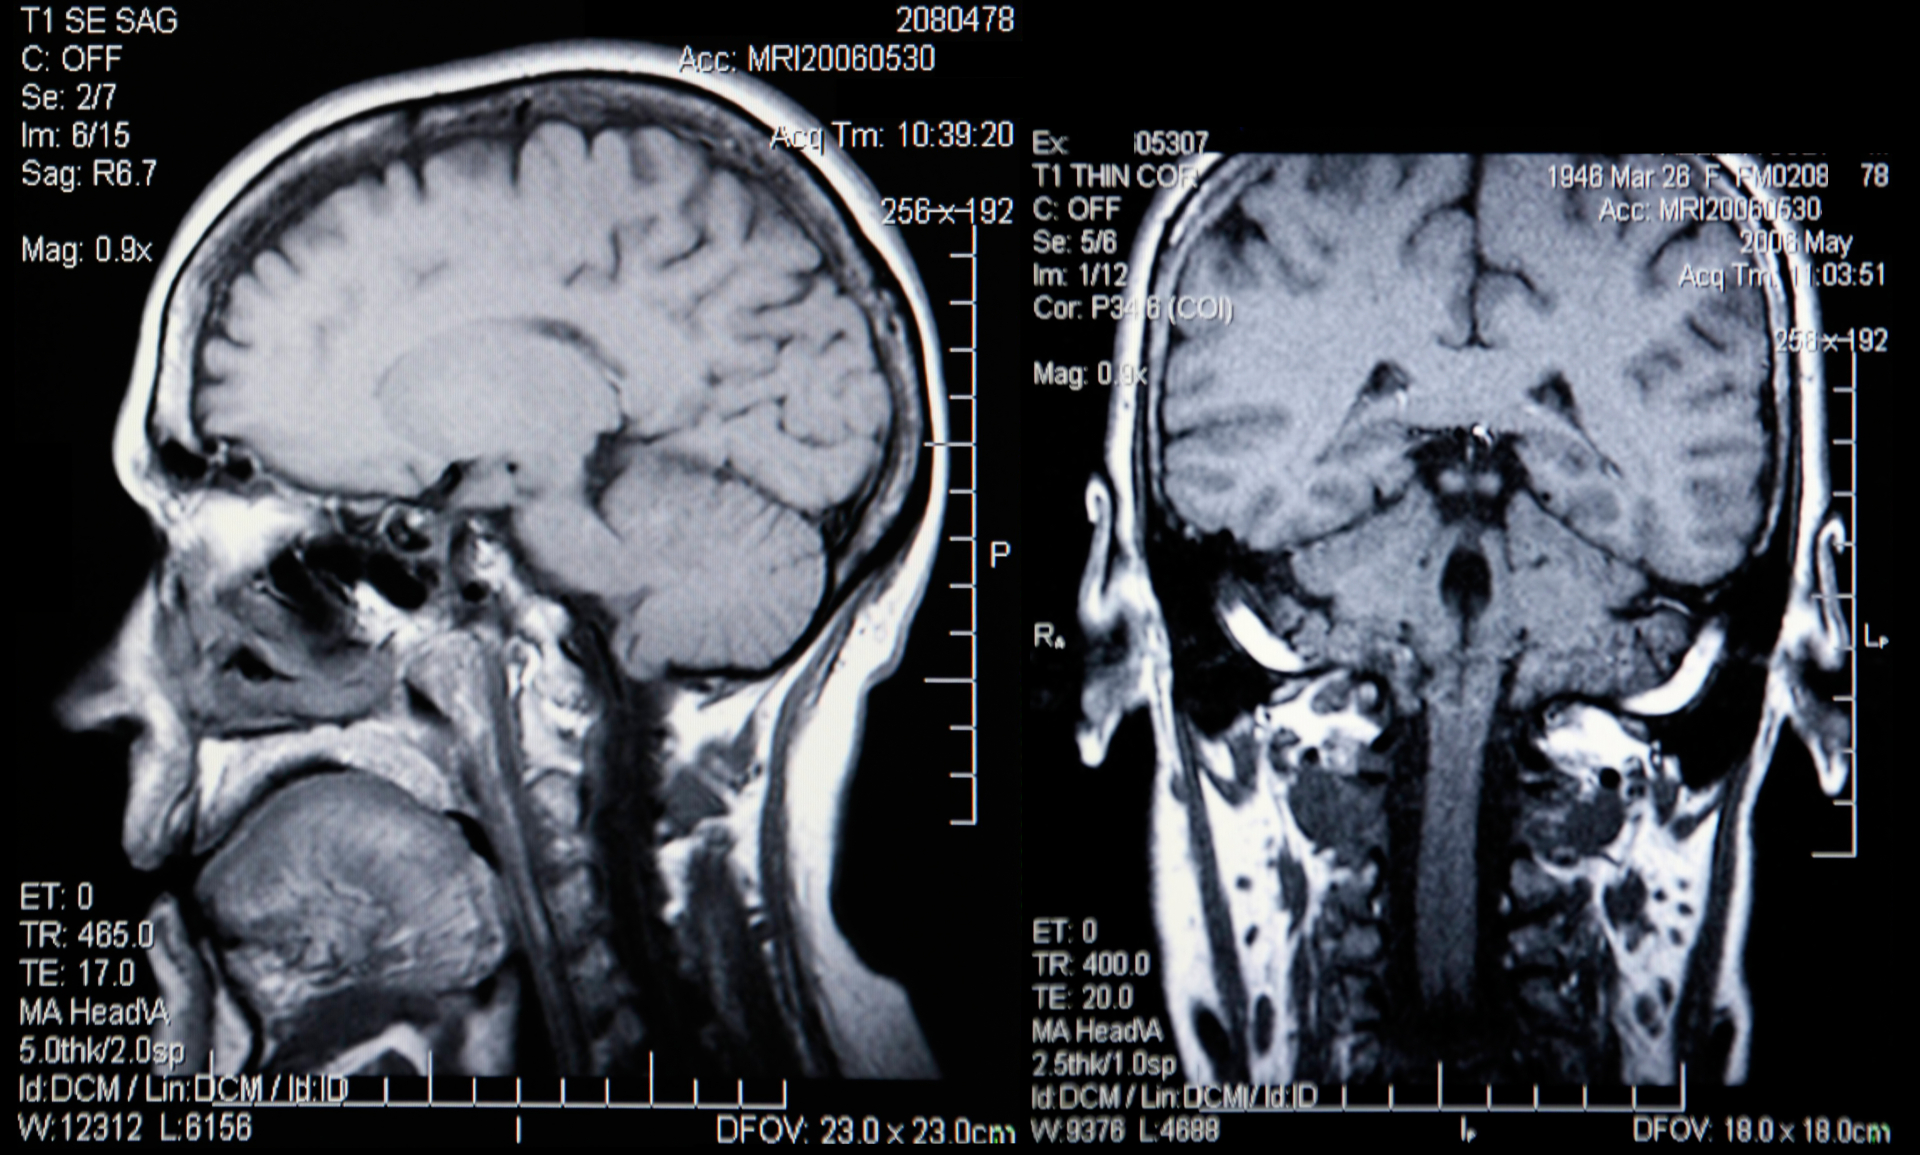

Hjärnans struktur kan avbildas med hjälp av en magnetundersökning eller datortomografi. En magnetundersökning ger mer detaljerad information om hjärnans struktur och innebär ingen strålningsexponering. Å andra sidan ger även en datortomografi exakt information om hjärnans struktur och kan vara enklare för patienten, eftersom det är en snabbare metod och avbildningen inte görs i ett rör utan i en böjd maskin. Datortomografi används också i situationer där en magnetundersökning inte är möjlig på grund av att patienten har vissa metalldelar eller en pacemaker inuti kroppen.

En bilddiagnostisk undersökning är en del av den diagnostiska processen. Avbildning används för att söka bekräftelse för den annars misstänkta demenssjukdomen. Dessutom kan man med hjälp av bilddiagnostiska undersökningar utesluta cirkulatoriska orsaker till minnessvårigheten och viktiga, behandlingsbara orsaker, som subduralblödning, cerebrovaskulära störningar och tumörer.

Enbart en bilddiagnostisk undersökning av hjärnan räcker inte för att ställa en diagnos, eftersom hjärnan är individuell, och åldrandet och många andra sjukdomar kan orsaka liknande fynd som demenssjukdomar. Å andra sidan utesluter inte åldersenliga eller normala bilddiagnostiska fynd demenssjukdom, särskilt i de tidiga stadierna av sjukdomen.